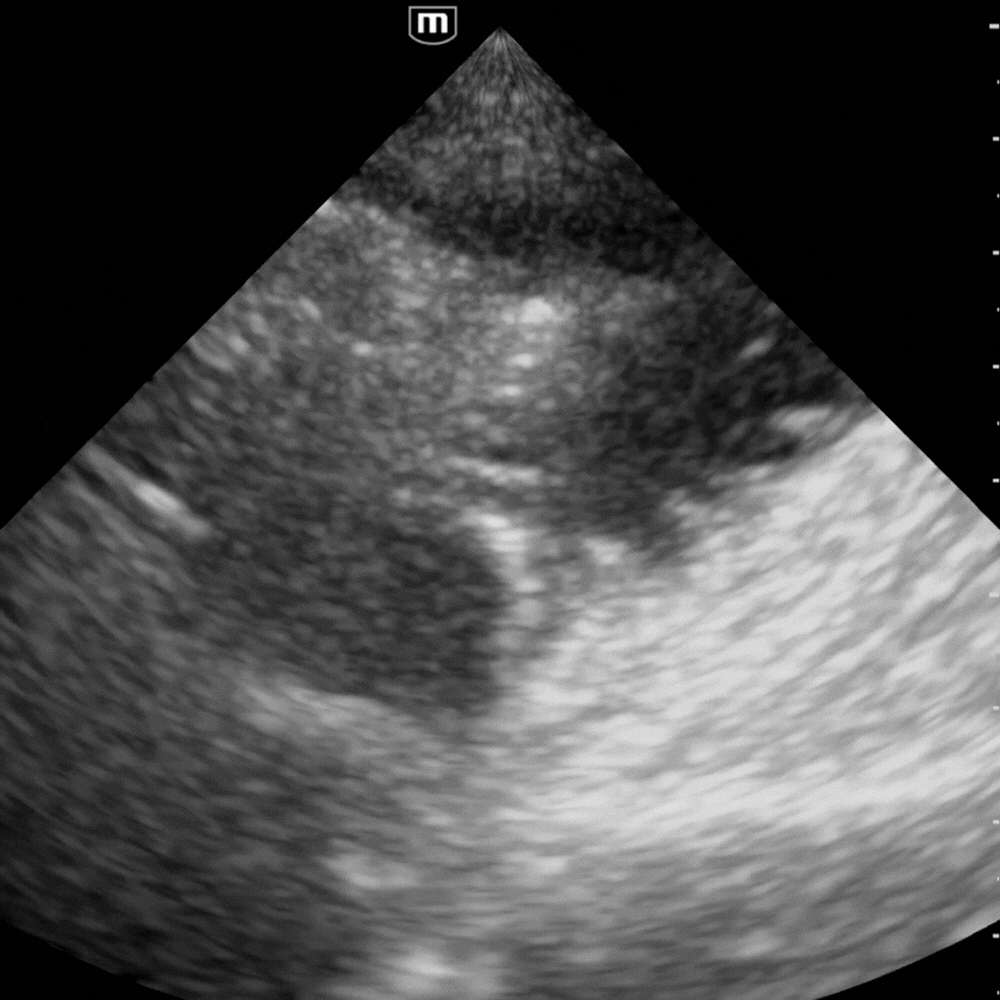

- Dilatation des anses grêles : diamètre > 25 mm (> 2,5 cm), contenu liquidien, paroi fine.

- Anses coliques : plus périphériques, contenu gazeux, haustrations visibles.

- Signe du tourbillon : mouvement de va-et-vient du contenu intestinal.

💧 Rechercher un épanchement inter-anse : marqueur de souffrance digestive.